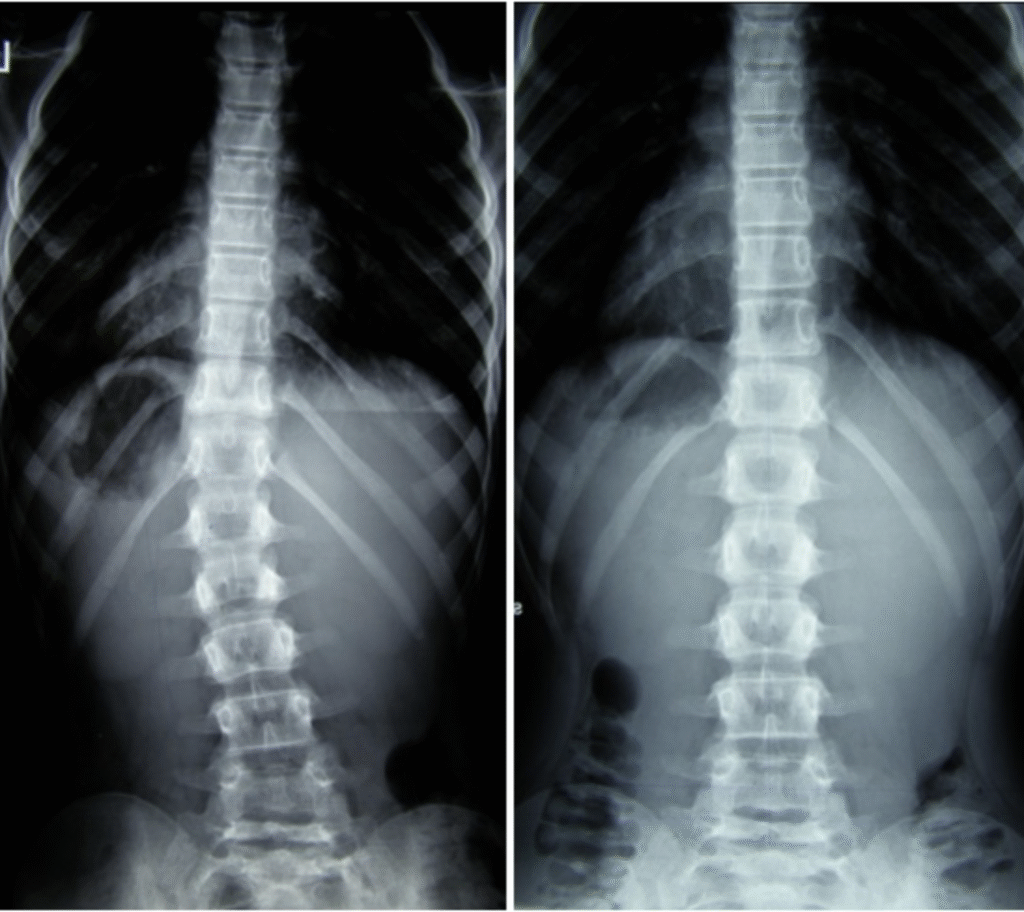

Maciej – 7 lat

Skolioza jednołukowa (statyczna) – zdj. z lewej. Korekcja uzyskana w trakcie jednej wizyty – zdj. z prawej

Dawid – 7 lat